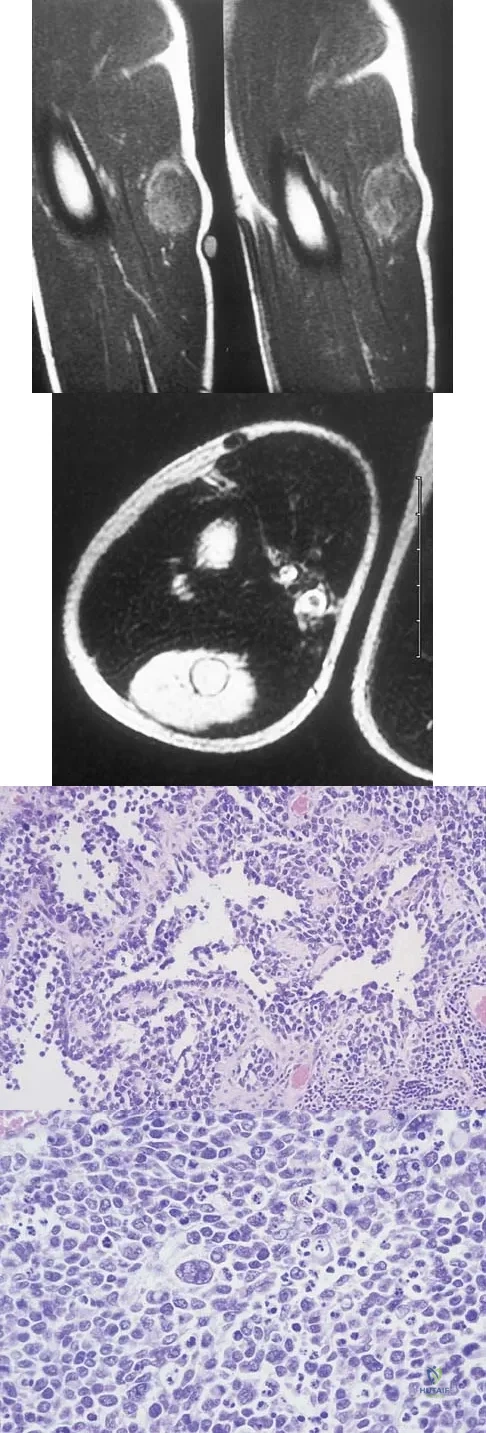

A 14-year-old boy has an asymptomatic mass on the right arm. MRI scans and biopsy specimens are shown in Figures 51a through 51d. Immunostaining is positive for desmin. Additional staging studies should include

A 13-year-old patient has foot drop and lateral knee pain. AP and lateral radiographs and an MRI scan are shown in Figures 49a through 49c. A biopsy specimen is shown in Figure 49d. What is the preferred method of treatment?